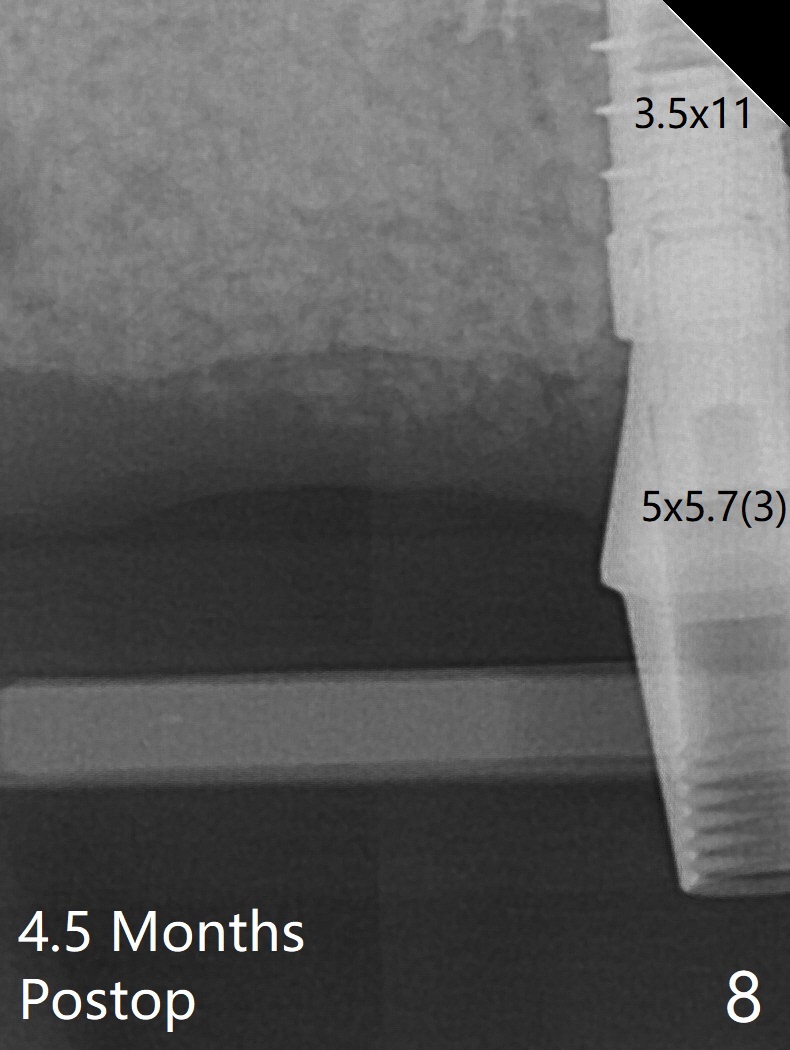

The patient returns for #4 extraction and immediate implant the 1st day clinic reopening after coronavirus lockdown. To reuse autogenous bone for #4 buccal gap closure, delayed implants are also placed at #13 and 14. It is much easier to determine the placement level of the immediate implant (open socket) with guide than that of the delayed ones (flapless) clinically. Immediate postop CT is taken for implant placement level confirmation (Fig.1-3). In fact the autogneous bone is too soft to be packed into #4 socket gaps. It has to be mixed with allograft to be packable. There is oozing when #14 healing abutment is placed. The hemorrhage is severe 4 days postop. The healing abutment is replaced by a healing screw. Hemostasis is achieved when the access is closed with GEM Cap and 4-0 Chromic gut suture. The patient will return for #3 extraction and socket preservation 1 month postop (Fig.4). To prevent postop hemorrhage, a cemented or temporary abutment will be placed at #4 before anesthesia, while .5 or 1.0 cc Augma bone will be placed at #3, covered with collagen plug and acrylic. In fact he cancels the appointment once because of symptom relief and will return 2 months postop. Sticky bone (Fig.5 *) and PRF is used at #3 for hemostasis, while a 5x5.7(3) mm pair (final) abutment is used to hold acrylic dressing in place. The latter remains in place with good oral hygiene 1 month postop (Fig.6 A: abutment). When the acrylic dressing is removed, the socket heals (Fig.7 K: the gingiva between the buccal and palatal sockets when the tooth was removed). The patient returns for impression 4.5 months postop. When the 5x5.7(3) mm abutment at #4 is reseated after cleaning, there is no horizontal gap between the abutment and implant in BW (Fig.8), while there is in PA (Fig.9). When a smaller abutment is seated (Fig.10), there appears to be a horizontal gap, whereas there is no vertical one. The situation is the same with #13 (Fig.11,12). The common denominator is 3.5 mm implant. With suspicion, BW is taken for the implant at #4 immediately before cementation (Fig.13). It appears that the abutment is most likely seated completely. There is no bone loss or screw loosening 4 months post cementation (Fig.14,15). One month later the patient agrees to have 3 lower implants to replace RPD.